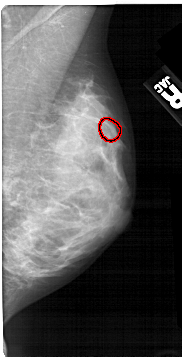

A_1345_1.LEFT_MLO

RIGHT_CC LINES 5041 PIXELS_PER_LINE 2566 BITS_PER_PIXEL 12 RESOLUTION 43.5 OVERLAY

FILE: A_1345_1.RIGHT_CC.OVERLAY

TOTAL_ABNORMALITIES 1

ABNORMALITY 1

LESION_TYPE CALCIFICATION TYPE PLEOMORPHIC DISTRIBUTION CLUSTERED

ASSESSMENT 4

SUBTLETY 4

PATHOLOGY BENIGN

TOTAL_OUTLINES 1

BOUNDARY